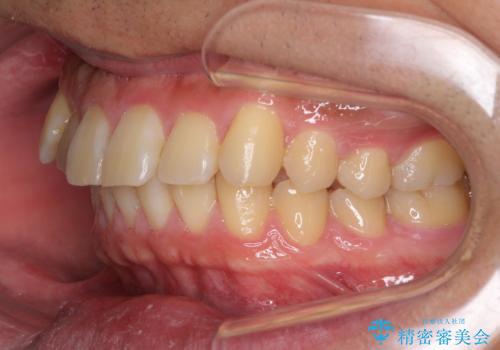

遠方からの通院 インビザライン矯正治療

- 20代男性

- インビザライン

- 前歯のデコボコを気にして来院された患者様です。

当院でインビザライン矯正治療をされている方からのご紹介ということで、インビザラインでの矯正治療をご希望でした。

ワイヤー矯正に比べ来院頻度は低いものの、新幹線での通院のため、やや治療期間が延びることが懸念されました。